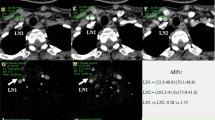

Two hundred and fifty-five LNs (143 non-metastatic and 112 metastatic) were enrolled and allocated to training and validation sets (7:3 ratio). Radiomics features were extracted from arterial and venous phase iodine maps, respectively. Radiomics signature was constructed based on reproducible features using the least absolute shrinkage and selection operator (LASSO) logistic regression algorithm with 10-fold cross-validation. Logistic regression modeling was employed to build models based on CT image features (model 1), radiomics signature (model 2), and the combined (model 3). A nomogram was plotted for the combined model and decision curve analysis was applied for clinical use. Diagnostic performance was assessed and compared. Internal validation was performed on an independent set containing 78 LNs.

Liu X, Ouyang D, Li H et al (2015) Papillary thyroid cancer: dual-energy spectral CT quantitative parameters for preoperative diagnosis of metastasis to the cervical lymph nodes. Radiology 275:167–176

Zhao Y, Li X, Li L et al (2017) Preliminary study on the diagnostic value of single-source dual-energy CT in diagnosing cervical lymph node metastasis of thyroid carcinoma. J Thorac Dis 9:4758–4766